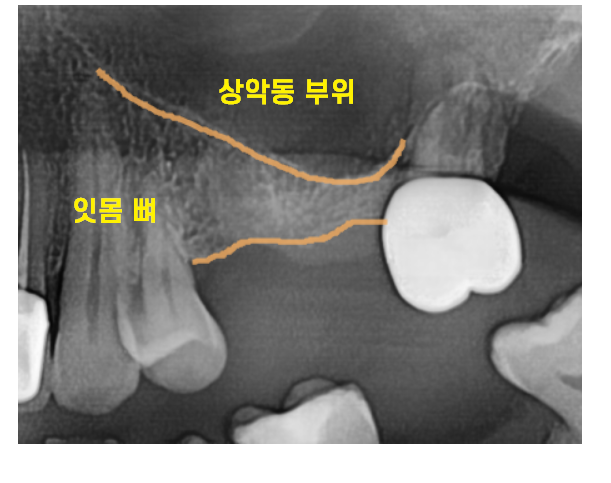

파노라마 사진상에서도 매우 얇아 보였습니다.

23.04.15

평면적인 정보 말고

앞뒤 좌우 3차원적인 자세한 분석을 위해

ct 촬영을 시행

디지털 기기의 분석 결과

3mm 정도의 아주 얇은 뼈가 확인되었습니다.

어금니 임플란트를 심기 위해서는

최소 8~10mm의 길이가 필요합니다.

어느 정도로 부족한지 감이 잡히시나요~?

게다가 상악동 공간에 염증까지...

비염이 심해서 생긴 것으로 추정

이비인후과 치료도 계속 받고 계신다 하셨어요.

상일동 임플란트 치료를 위해

부족한 잇몸뼈를 보충해 주는 수술이 필요했습니다.

이것이 바로 상악동 거상술인데요.

상악동이라는 구조물을 들어 올려

뼈이식을 하는 거죠